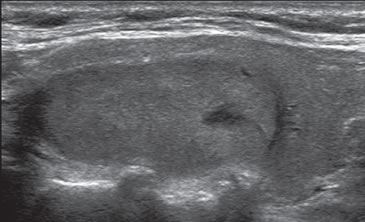

Patrón indeterminado o neoplásico

Son tumores sólidos, únicos, iso o hiperecogénicos, muy homogéneos, encapsulados, de contornos lisos, de forma ovoidea, sin microcalcificaciones (Figura 3b). En el 80% de los casos se puede observar un halo hipoecogénico. Ocasionalmente pueden ser discretamente hipoecogénicos. La vascularización habitualmente esta aumentada en la periferia con vasos que se descuelgan hacia el centro de la lesión (Figura 12). A diferencia de los nódulos coloideos generalmente no se observan imágenes quísticas (Figura 32).

En este grupo se encuentran principalmente las neoplasias foliculares benignas (adenomas) o malignas (carcinomas). Están compuestos de células foliculares o células de Hurthle en distinta proporción, y son encapsuladas. La mayoría (85%) corresponden a adenomas foliculares. Sin embargo, con el mismo patrón se puede presentar el carcinoma folicular bien diferenciado, aunque este suele ser de mayor tamaño, hipoecogénico, de contenido más heterogéneo, la capsula de mayor espesor (Figura 33a y b) y el aumento de la vascularización es difuso22. La presencia de calcificaciones intranodulares conlleva mayor riesgo de malignidad.

En la práctica, todos los nódulos con patrón neoplásico van a ir necesariamente a PAAF para poder determinar su etiología. De estos, al menos 50% van a ser benignos y entre 5%-15% van a ser carcinomas foliculares. Dentro de este grupo, un porcentaje menor va a corresponder a cáncer papilar variedad folicular21.